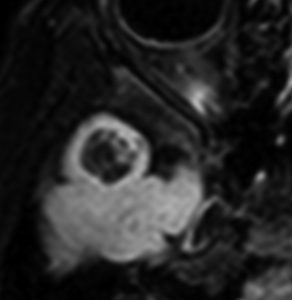

右側頭葉先端の腫瘍です。発症時にはMRIで異常所見がありませんでしたが,徐々に顕在化しました。ガドリニウム増強はなく一部のう胞性です。

4歳時に意識現存を伴う発作が1日3回くらいあるという難治性部分てんかんで発症しました。手術中の頭蓋内脳波で,下側頭回に激しい棘波と棘律動を認め,扁桃体への刺入電極でも棘波がありました。周辺脳にも棘波はありましたが,病変(腫瘍)と扁桃体を切除するのみの手術を行いました (lesionectomy and amygdalectomy)。手術後13年が経過しますが発作はありません。病理では,腫瘍組織内に神経節細胞はなく,皮質異形成 cortical dysplasiaあるいはグリオーマ様病変 gliomatous lesionという診断でした。1p/19qに欠失はありませんでしたが,乏突起膠腫も否定できない周囲灰白質に浸潤性の腫瘍でした。この例はlow-grade gliomaでしょうが確定病理診断はできないものです。どちらであっても,基本的にグレード1ですから,手術後再発はしません。